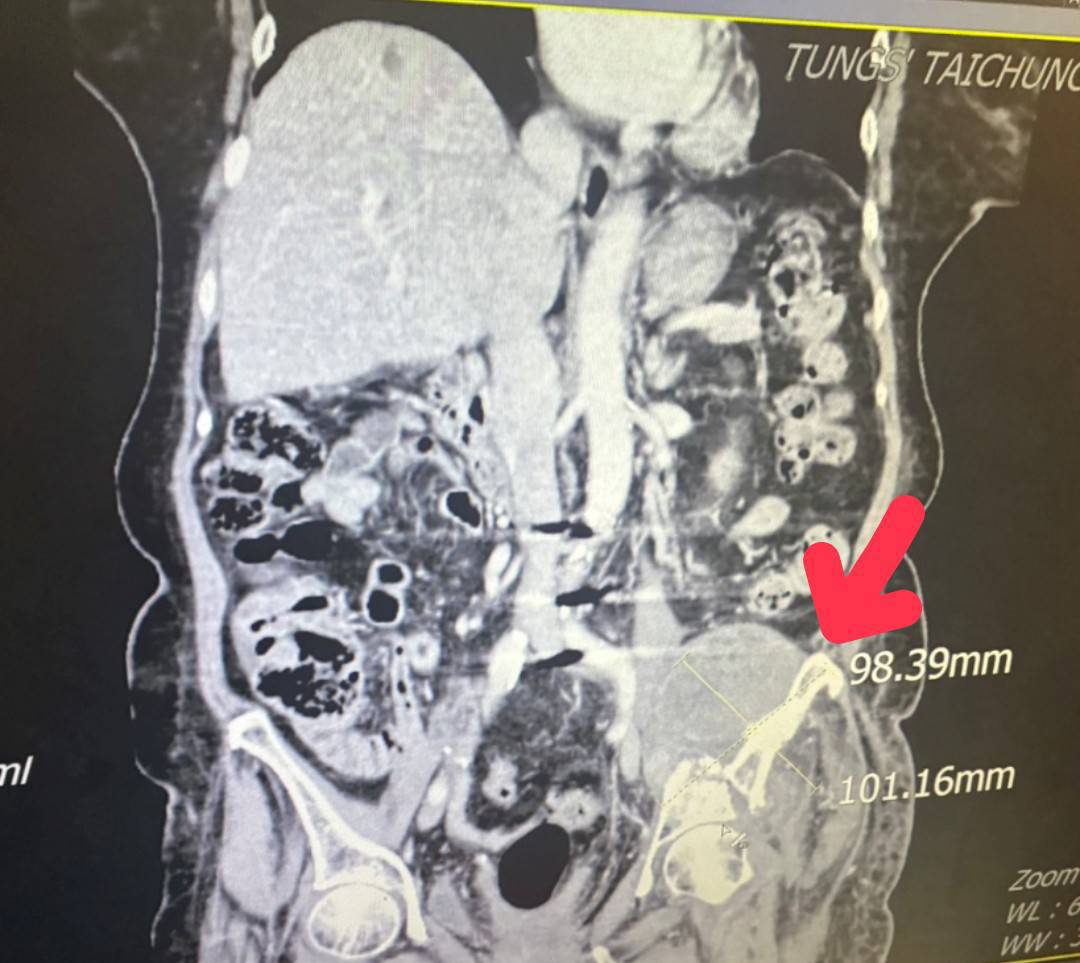

童綜合醫院指出,因腫瘤細胞直徑平均約15公分,腫瘤位置執行手術風險過高,轉由放射腫瘤科葉啟源主任進行銳視刀適應性放射治療,利用空間分割點狀治療方式在局部的位置給予點狀高劑量的放射線,再配合傳統銳視刀治療方式,經過一個月26次治療後,腫瘤已經縮小至9.8公分x10.1公分左右,縮小腫瘤後也讓疼痛獲得明顯改善。

放射腫瘤科葉啟源主任表示,肝樣癌是一種罕見且具高度侵襲性的惡性腫瘤,特點是發生在肝臟以外器官的原發性腫瘤,但組織型態與細胞特徵卻與「肝細胞癌」相似。個案的腫瘤發生位置在骶骨(尾椎上方)。因為初期無任何不適症狀,等到腫瘤大到壓迫到骶叢神經而導致腿部疼痛與無力才發現,因腫瘤太大,若只採用一般治療無法有效消除癌細胞,因此搭配使用最新的點狀式治療,以高劑量消融巨大、抗放射性腫瘤,同時利用傳統治療劑量梯度保護周圍的健康組織與器官。讓腫瘤明顯在三個月內縮小了2×7公分,緩解骶叢神經受壓迫的情況,改善患者的疼痛與行動能力。